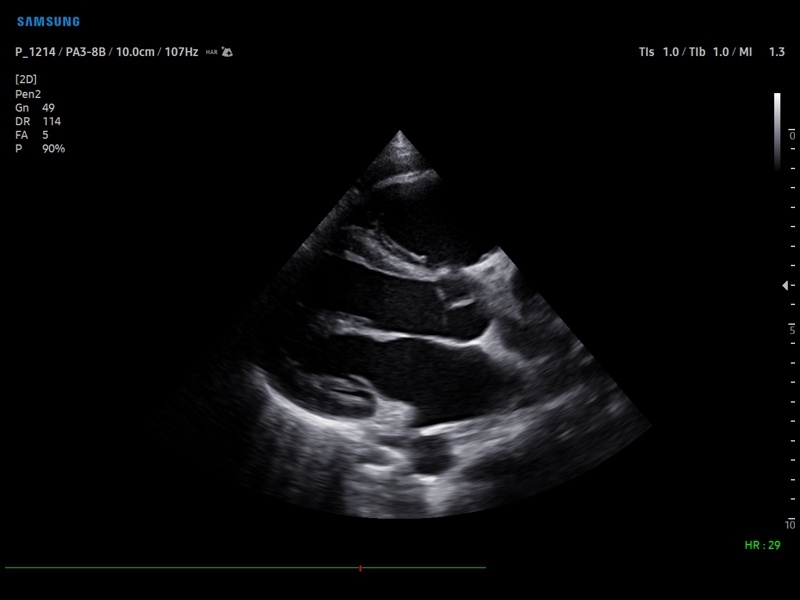

• Кардиология

• M - одномерный режим для исследования сердца, анатомический М-режим (необходим кардиопакет), CM - цветной М-режим (необходим кардиопакет).

• Кардиопакет: тканевый допплер (TDI) + анатомический М-режим + цветной М-режим (CM) + программное обеспечение.

• Пакет кардиологических исследований.

М-режим:измерение диаметра аорты, передне-заднего размера ЛП, толщины МЖП (систолическая и диастолическая), толщины ЗСЛЖ (систолическая и диастолическая), размеров ЛЖ и ПЖ (систолический и диастолический), ФВ (Teichholz).

B-режим:измерение диаметра аорты (восходящей, дуги, нисходящей, на уровне синусов Вальсальвы, на уровне створок аортального клапана), определение размеров ЛП и ПП (максимальный, минимальный, систолический, диастолический, переднее-задний, верхнее-нижний, медиально-латеральный), расчет объемов ЛП и ПП, объемов ЛЖ (метод "Площадь-Длина", метод дисков (Simpson)), массы миокарда ЛЖ, индекса массы миокарда ЛЖ.